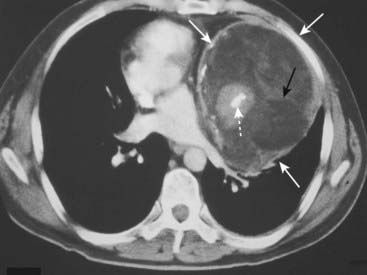

image On CT-PA, acute pulmonary emboli appear as partial- or complete-filling defects centrally located within the contrast-enhanced lumina of the pulmonary arteries (Fig. 12-21).

image

Figure 12-20 Hampton hump.

There is a wedge-shaped, peripheral air-space density present (dotted white arrow) associated with filling defects in both the left and right pulmonary arteries (solid white arrows). The wedge-shaped infarct is called a Hampton hump. Without the associated emboli present, the pleural-based airspace disease could have a differential diagnosis that includes pneumonia, lung contusion, or aspiration.

Figure 12-21 Saddle and peripheral pulmonary emboli.

Acute pulmonary emboli appear as partial or complete filling defects centrally located within the contrast-enhanced lumina of the pulmonary arteries. A, A large pulmonary embolus almost completely fills both the left and right pulmonary arteries (solid white and black arrows). This is a saddle embolus. B, A small, central filling defect is seen in a more peripheral pulmonary artery (dotted white arrow). This pulmonary artery seems to be floating disconnected in the lung because the plane of this particular image does not display its connection to the left pulmonary artery.